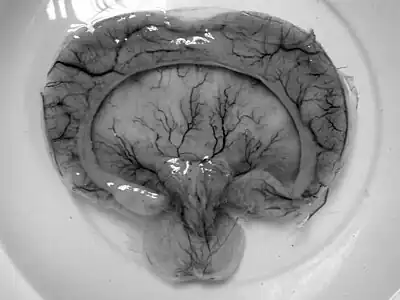

• Alobar holoprosencephaly, the most serious form, in which the brain fails to separate, is usually associated with severe facial anomalies, including lack of a nose and the eyes merged to a single median structure (see cyclopia).

• Semilobar holoprosencephaly, in which the brain's hemispheres have somewhat divided, is an intermediate form of the disease.

• Lobar holoprosencephaly, in which there is considerable evidence of separate brain hemispheres, is the least severe form. In some cases of lobar holoprosencephaly, the patient's brain may be nearly normal.

• Syntelencephaly, or middle interhemispheric variant of holoprosencephaly (MIHV), in which the posterior frontal lobe and the parietal lobe are not properly separated, but the rostro basal forebrain properly separates; it is possible that this is not a variant of HPE at all, but it is currently classified as such.[2]